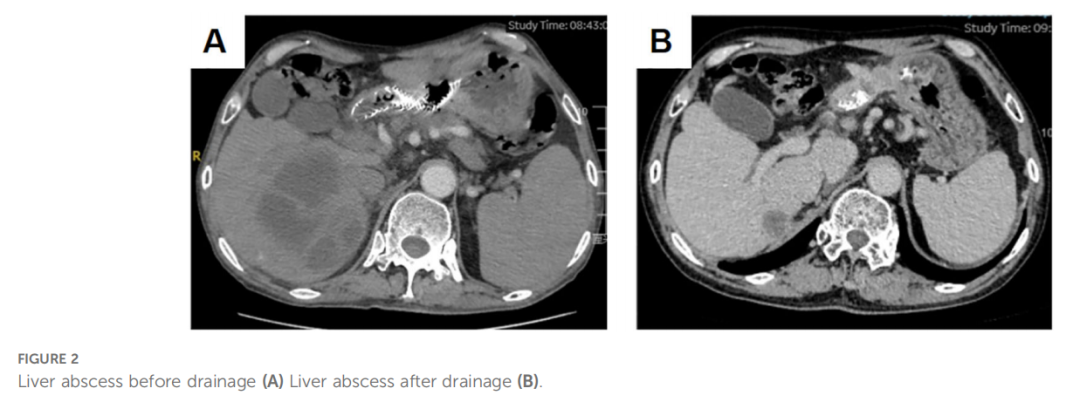

鉴于多线治疗失败,特别是对PD-1抑制剂纳武利尤单抗的耐药,患者进入四线治疗。首先尝试卡度尼利单抗单药治疗,3个月后评估为疾病稳定(SD),但病灶有轻微增大。随后,在卡度尼利单抗基础上加用阿帕替尼。联合治疗6个月后,影像学显示原发灶和肝转移灶显著改善,达到部分缓解(PR)(图1I、J)。治疗期间,患者出现肝脓肿(图2A),经穿刺引流和抗生素治疗后好转(图2B)。截至报告时,联合治疗已持续20个月,患者症状明显改善,多处转移灶缩小甚至消失,仍在随访中。患者的肿瘤标志物变化和治疗时间线总结见图表(表1,图3)。

▲图2 肝脓肿引流前(A)与引流后(B)对比